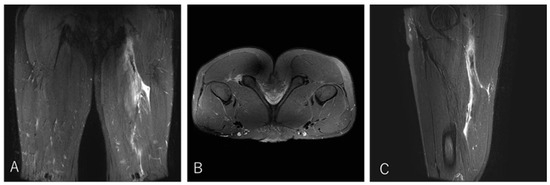

Impact of Proximal Conjoint Tendon Injury on Return to Play in the BF–ST Complex: A Prospective MRI-Based Study

by Makoto Wada, Takumi Okunuki, Takeshi Sugimoto, Yasuhito Tanaka and Tsukasa Kumai

Background/Objectives: Proximal hamstring injuries involving the biceps femoris–semitendinosus (BF–ST) conjoint tendon (CT) often exhibit delayed healing, yet the prognostic significance of CT involvement and intratendinous injury morphology has not been fully clarified. This study aimed to determine whether full-layer CT injury, particularly bilateral [...] Read more.

Background/Objectives: Proximal hamstring injuries involving the biceps femoris–semitendinosus (BF–ST) conjoint tendon (CT) often exhibit delayed healing, yet the prognostic significance of CT involvement and intratendinous injury morphology has not been fully clarified. This study aimed to determine whether full-layer CT injury, particularly bilateral involvement in Zone C, prolongs return-to-play (RTP) in competitive rugby athletes. Methods: This prospective study evaluated 41 university rugby players with acute BF–ST complex injuries using clinical examination, ultrasonography, and MRI. Injuries were classified by Type (I: full-layer CT; II: BFLH-only; III: ST-only), Zone (A–E), and Grade (0–3). RTP was defined as unrestricted return to team training or match play. Group differences were analyzed using ANOVA or non-parametric tests with appropriate post hoc corrections. Results: Type I injuries required significantly longer RTP (11.4 ± 4.8 weeks) than Type II (5.3 ± 2.4 weeks) and Type III (4.0 ± 1.7 weeks), confirming the strong impact of CT involvement on prognosis. In Zone C, bilateral full-layer CT involvement was associated with an approximately twofold longer RTP duration compared with unilateral BFLH-side injuries, indicating that intratendinous tissue disruption influences recovery. These findings highlight the importance of early MRI-based assessment to identify clinically relevant tendon involvement patterns. Conclusions: Full-layer CT injuries, particularly bilateral intratendinous patterns in Zone C, markedly prolong RTP compared with isolated BFLH or ST injuries. An MRI-based classification incorporating injury type, zone, and extent of CT involvement provides clinically valuable prognostic information and may enhance RTP decision-making. Full article

Show Figures

Figure 1